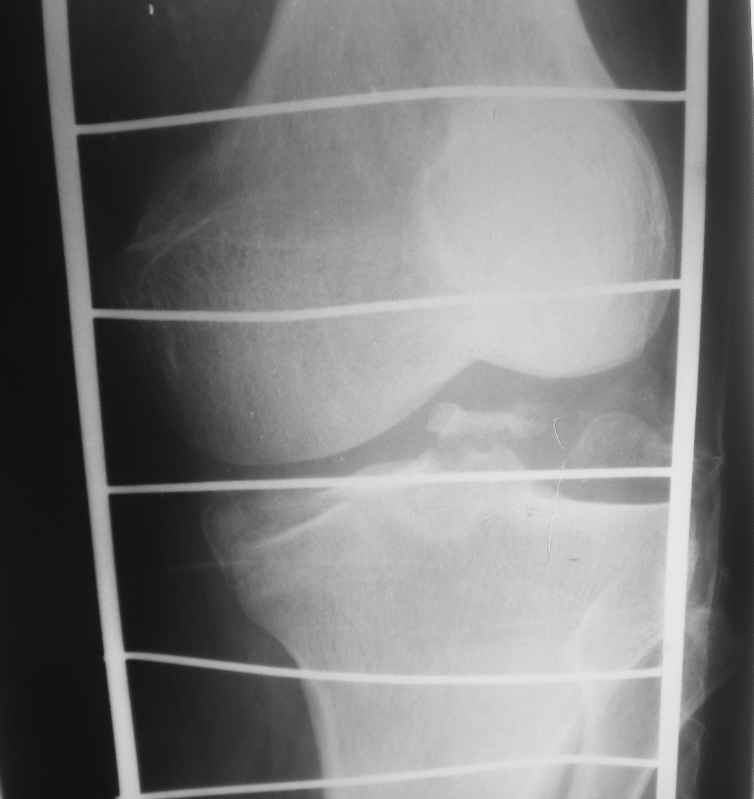

[Ortho] Помогите определиться - перелом мыщелков правой большеберцовой кости

Высылаю рентгенограммы